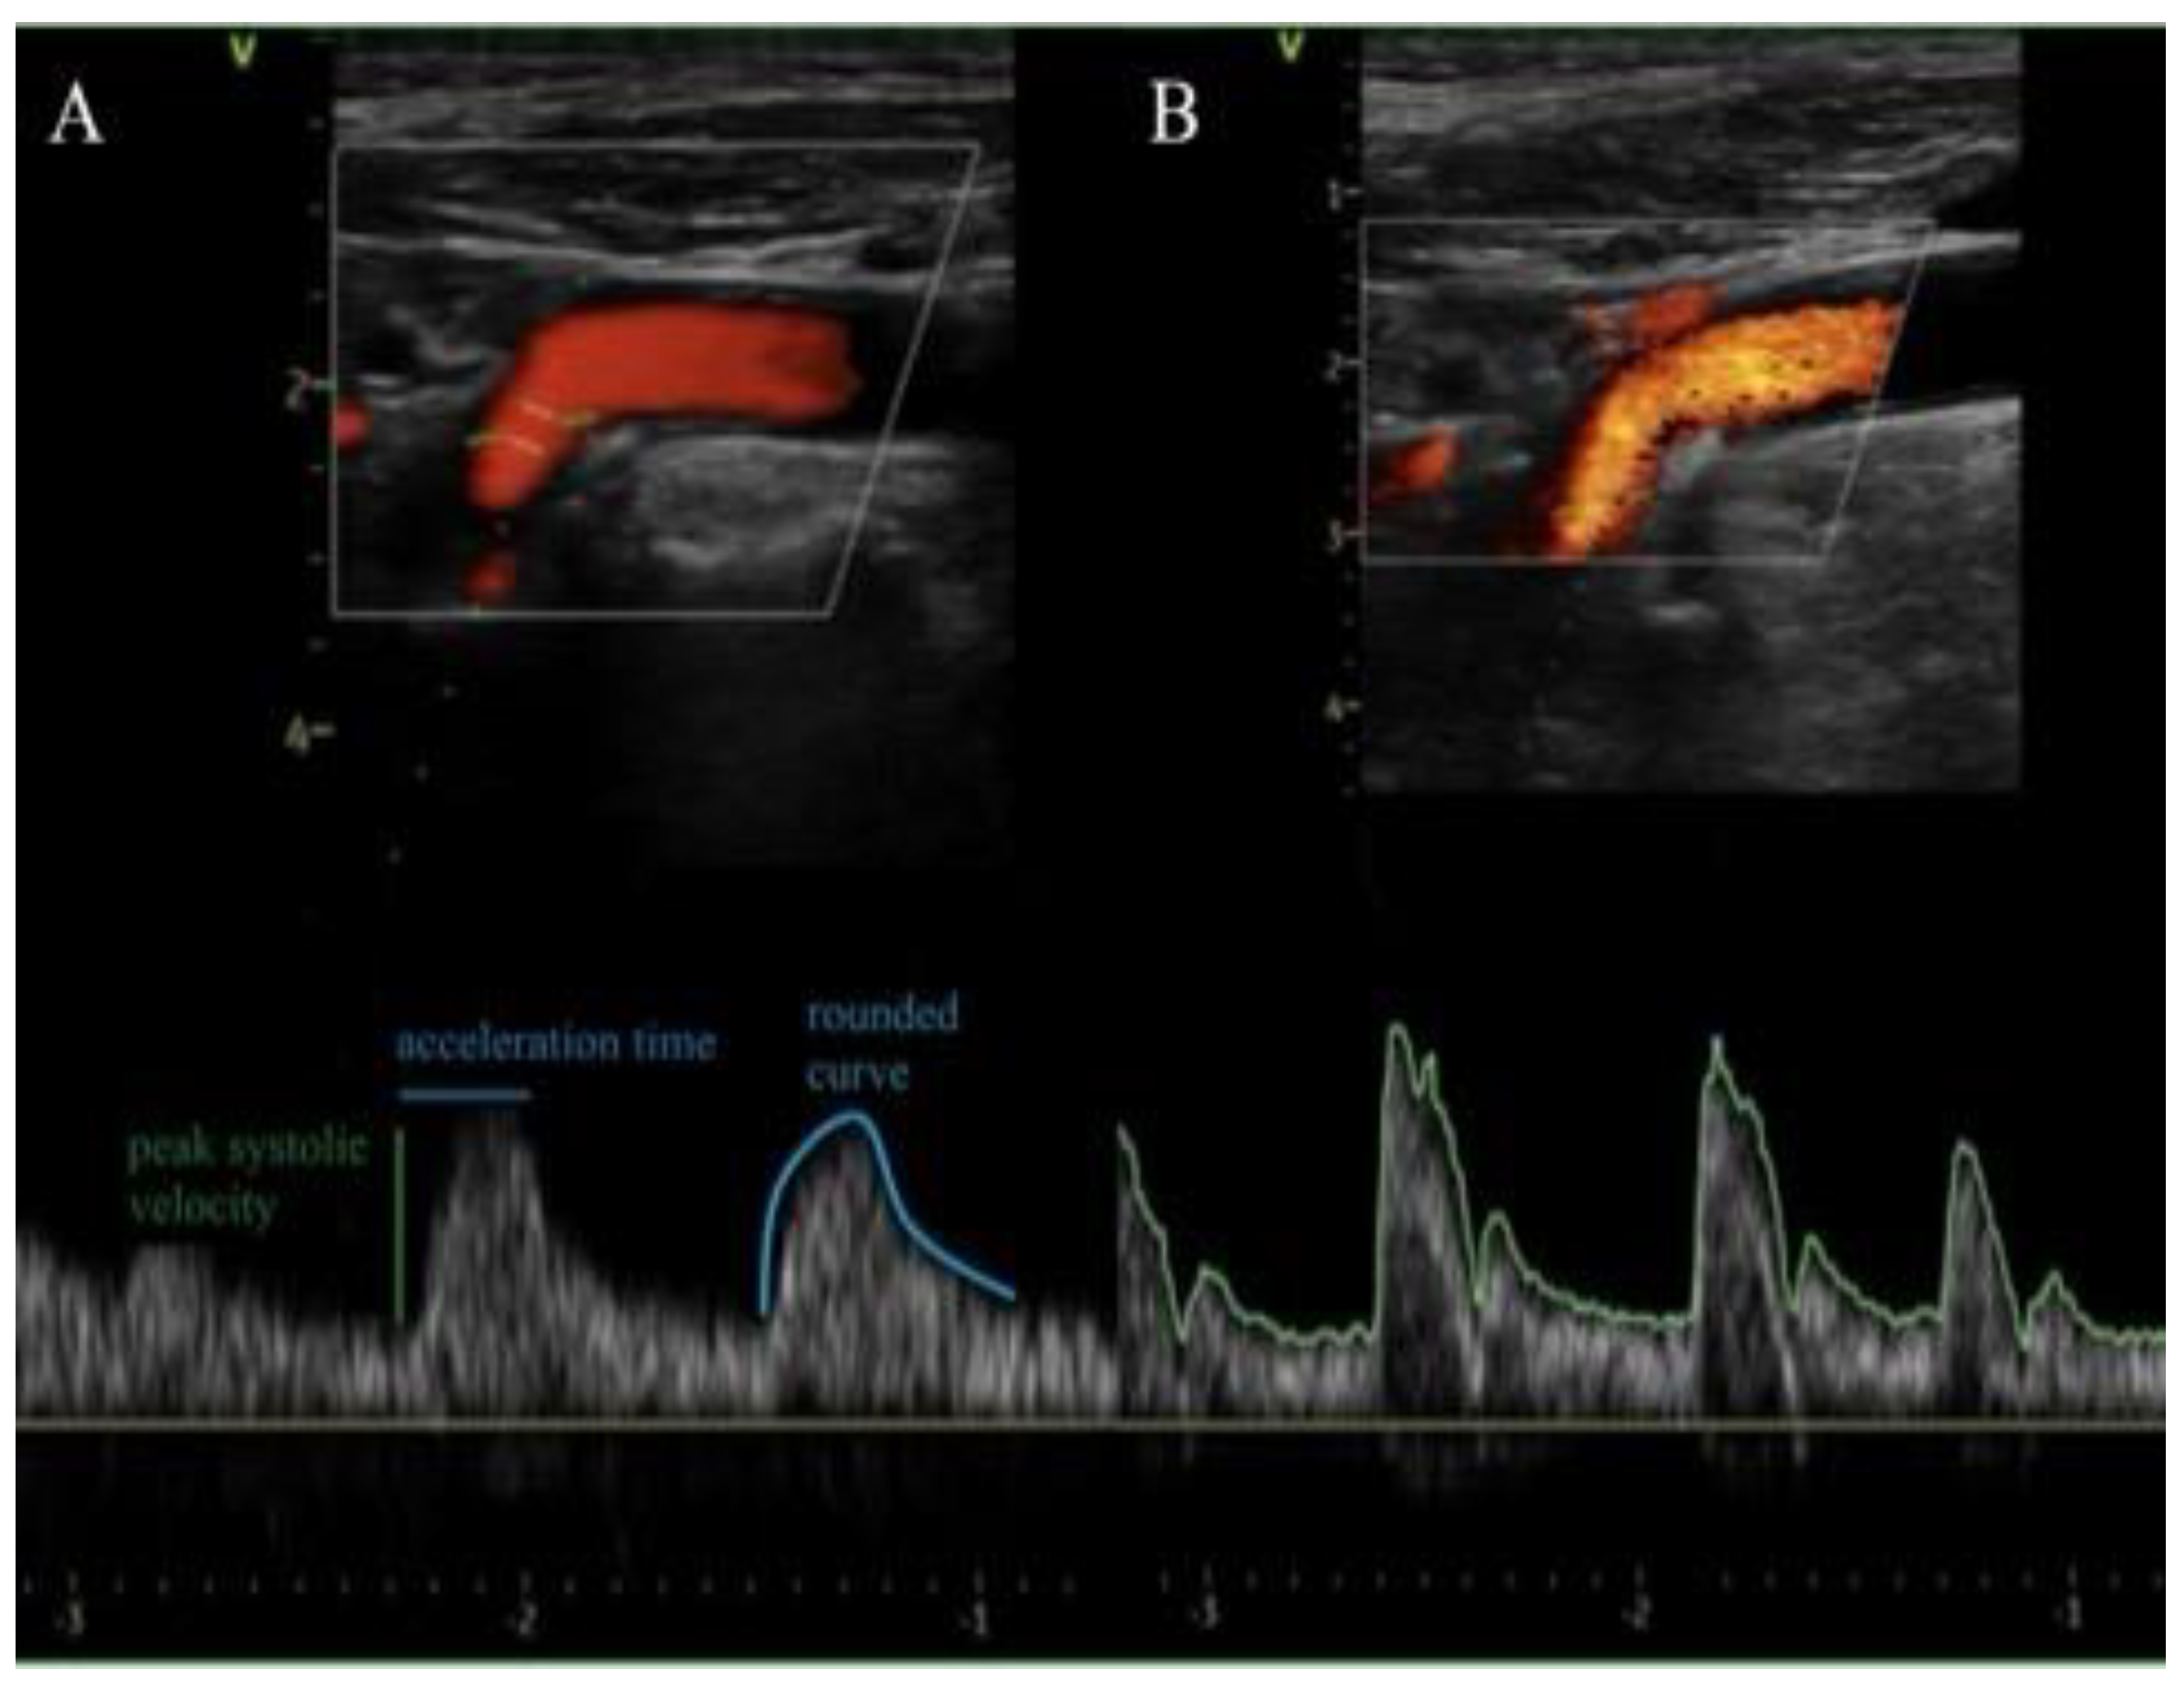

| CCA AT (s) | 0,168 (±0,05) | 0,112 (±0,04) | -50 | 0,01 |

| ICA AT (s) | 0,177 (±0,05) | 0,124 (±0,04) | -42 | 0,01 |

| VA AT (s) | 0,160 (±0,05) | 0,115 (±0,05) | -39 | 0,02 |